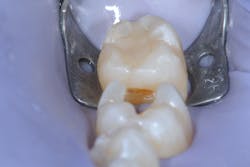

A 27-year-old patient was referred to me due to discomfort associated with dentinal hypersensitivity secondary to erosion on his posterior teeth (figure 1 above: Initial presentation. Note the exposed dentin due to erosion). His former dentist suggested crown lengthening due to inadequate space for full-coverage crowns.

After a thorough evaluation of his clinical presentation, radiographs, and intraoral scan, it was evident that the discomfort was due to exposed dentin. The intraoral scan confirmed there was adequate interocclusal space to restore the eroded tooth structure with a minimally invasive approach (figure 2). All options were reviewed with the patient, and it was mutually agreed upon to address his chief complaint in this manner. Proper isolation is critical for reliable bonding.